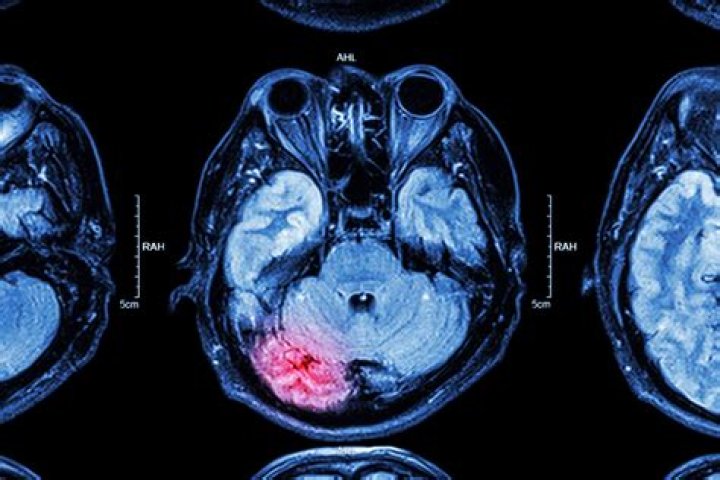

Traumatic brain injury (TBI) is sudden damage to the brain caused by a blow or jolt to the head. Common causes include car or motorcycle crashes, falls, sports injuries, and assaults. Injuries can range from mild concussions to severe permanent brain damage.